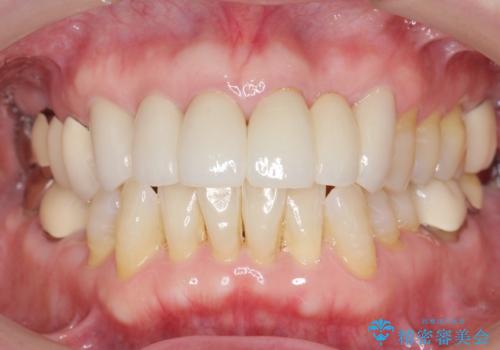

金属を使わないジルコニアセラミッククラウンの自然な仕上がりにご満足頂けました。

また、古い被せ物はブリッジではない右上321も連結されていましたが、1本1本の歯の動揺がなく連結する必要がないと判断し単冠による補綴を行いました。

単冠の部位は天然歯のようにフロスを通すことができるため、セルフメンテナンスもしやすくなったと患者様に喜んで頂けました。

被せ物の種類:ジルコニアセラミッククラウン スタンダード